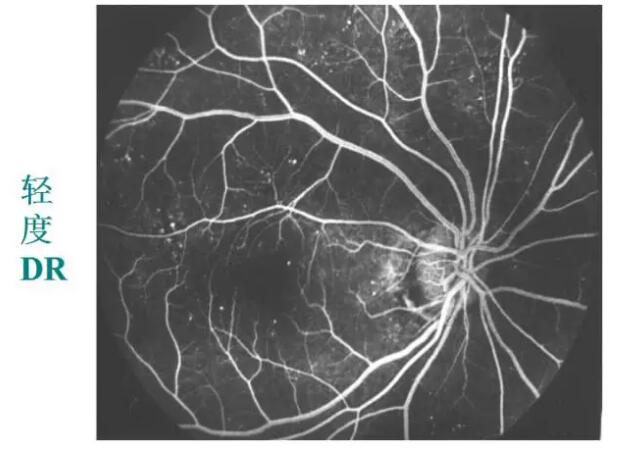

糖网病的眼底表现

微血管瘤

出血斑

渗出

视网膜静脉扩张、动脉变细、小血管闭塞

糖网病的检查手段

眼底荧光血管造影:更清楚、更敏锐